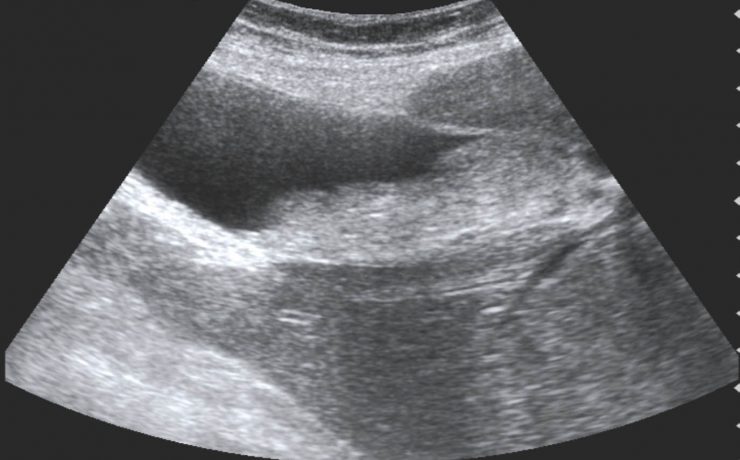

Marcadores ultrasonograficos para enfermedades genéticas

El síndrome de Down es una malformación congénita causada por una alteración del cromosoma 21 (trisomía del par 21) que se acompaña de retraso mental moderado o grave. Debe su nombre a John Langdon Haydon Down quién fue el primero que describió esta condición en 1866, Las personas con síndrome